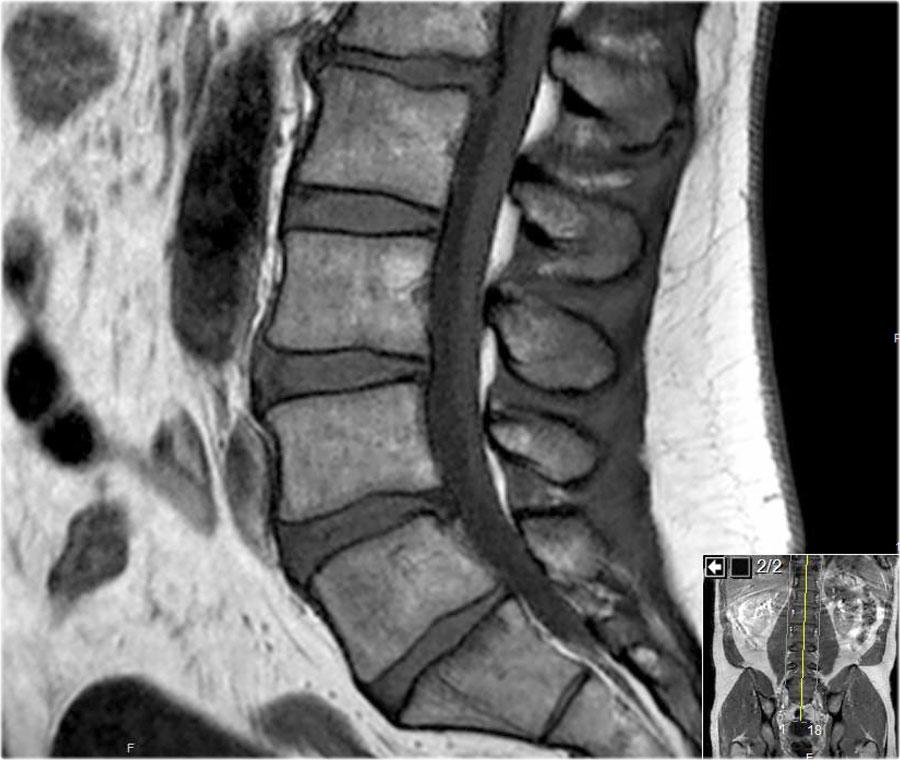

Các hình ảnh cắt dọc chuỗi xung T1W cung cấp nhiều thông tin chẩn đoán nhất.

Trước khi bắt đầu tìm kiếm bất kỳ thoát vị nào, hãy quan sát kỹ các mô trước cột sống và tủy xương.

Khi đã phát hiện bất thường, hãy đối chiếu các phát hiện này với hình ảnh chuỗi xung T2W (hình).